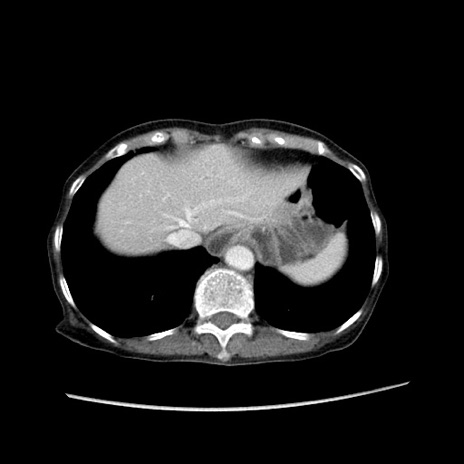

症例25(横断像)

【症例】80歳代女性

【主訴】胸のつかえ感

【現病歴】約9時間前に食後から胸のつかえた感じあり、嘔吐あり、来院。

【既往歴】胃癌(全摘)、胆摘、虫垂炎

【身体所見】心窩部に圧痛あり、反跳痛なし。

【データ】WBC 5700、CRP 0.05